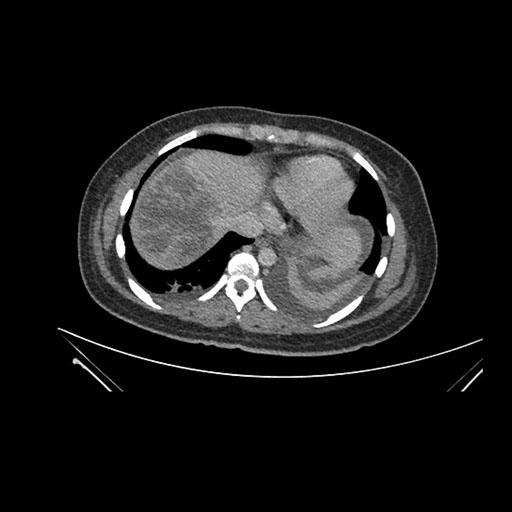

Imaging Analysis

Look through the patient's CT scan to identify any areas of concern for the necessary procedure.

Axial Venous

Based on initial findings, which issue(s) would you be most concerned about?